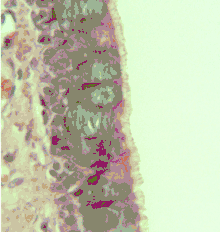

Cross-section of pseudostratified columnar epithelium